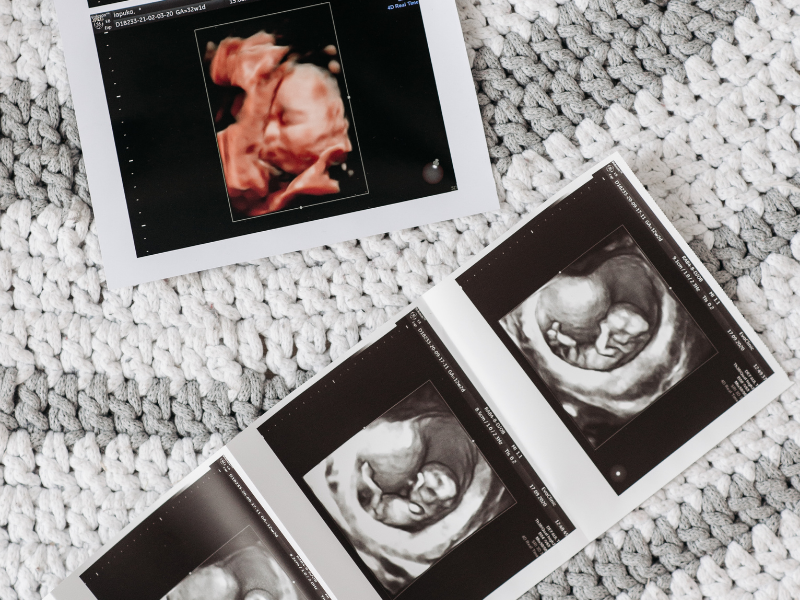

Gebelik süreci, hem anne hem de fetüs sağlığının izlenmesi açısından titizlikle takip edilmesi gereken bir dönemdir. Ultrasonografi (USG), gebelikte en sık kullanılan görüntüleme yöntemlerinden biridir. İkinci basamak ultrasonografi ise daha detaylı bir inceleme sağlayarak gebelik sürecinde önemli bir yer tutar.

İkinci basamak ultrasonografi, genellikle gebeliğin 18-24. haftaları arasında yapılan ve detaylı bir fetal değerlendirme sağlayan ileri düzey bir ultrasonografidir. Bu inceleme, bir perinatolog veya bu alanda uzmanlaşmış bir radyolog tarafından gerçekleştirilir. İkinci basamak ultrasonografi, standart ultrasonografiden daha ayrıntılıdır ve özellikle aşağıdaki durumlarda önerilir: